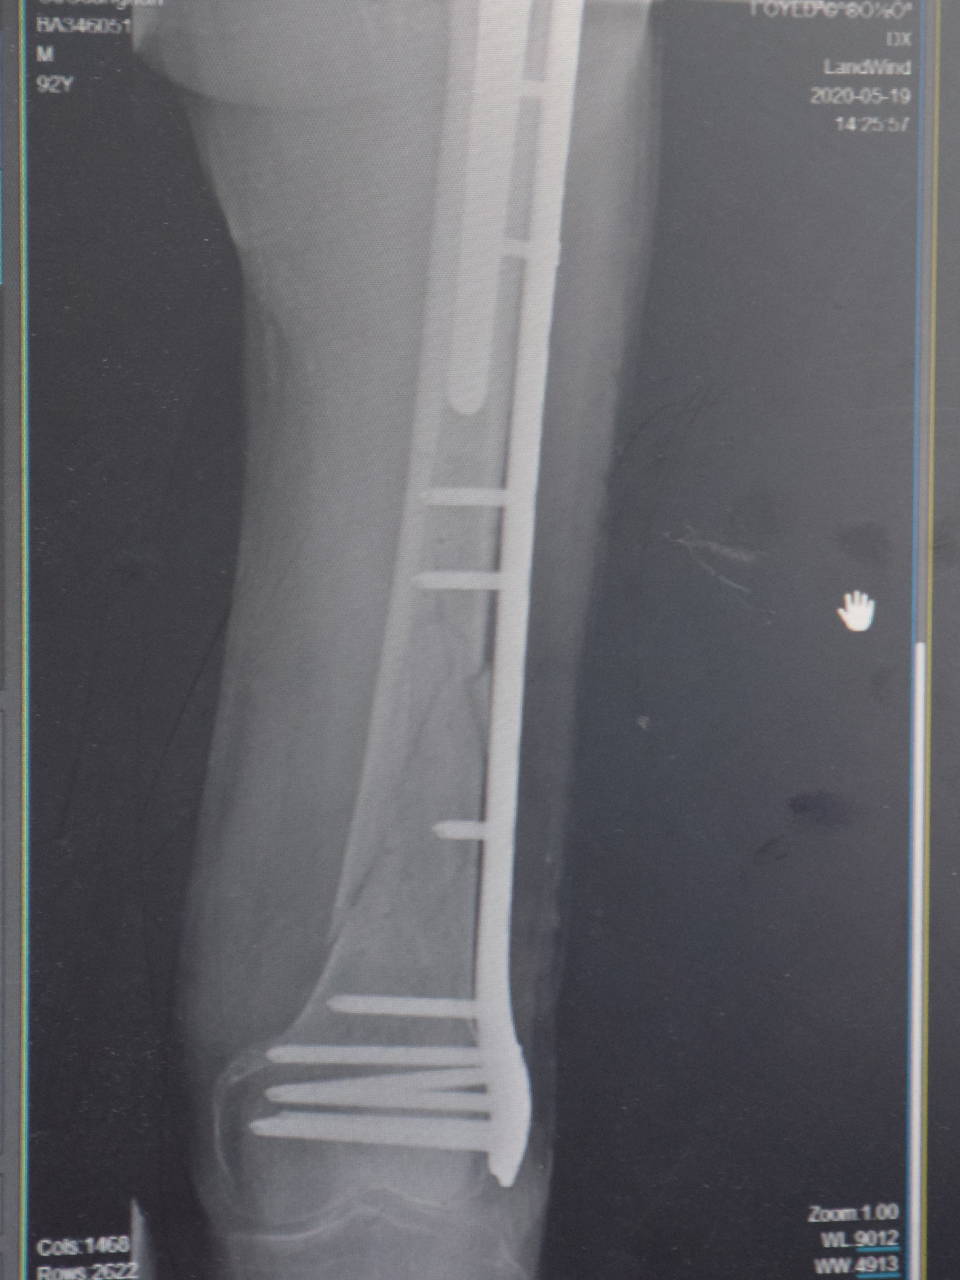

关节影像

早在18年10月份,大爷因左腿髋关节股骨粗隆间骨折,在台州市博爱医院做了人工骨头置换,也是陈医生做的手术。大爷身体健朗,手术恢复的很好,不久也就在医院的安排下出院了。